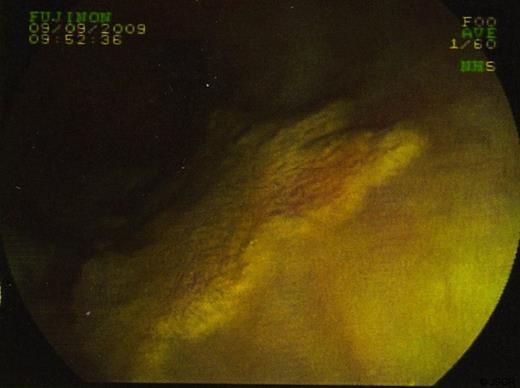

Biopsies were taken and sent to histopathology. In some sections the cells viewed had small bland nuclei with foamy cytoplasm. They were negative for mucin stain and negative for epithelial markers. There was no dysplasia or malignancy. This picture was consistent with xanthalasma. Other biopsies of surrounding tissue showed a picture consistent with Barrett’s oesophagus. (Figure 3 & 4)